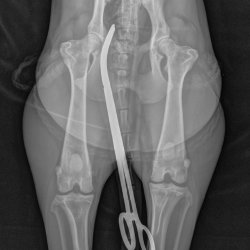

RTG snímek Rocky